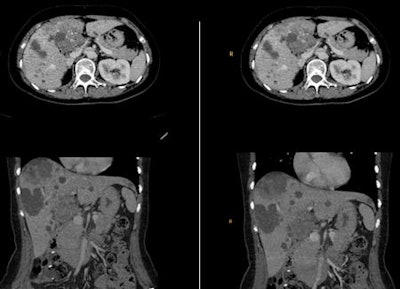

For the clinical evaluation, the researchers performed low-dose CT on cancer patients who had had a previous full-dose examination. The body mass index (BMI) CT protocol was modified so that patients received the next CT scan at one BMI/dose level lower. They obtained a dose reduction of about 50%, while retaining an image quality at least equal to the full-dose examination.